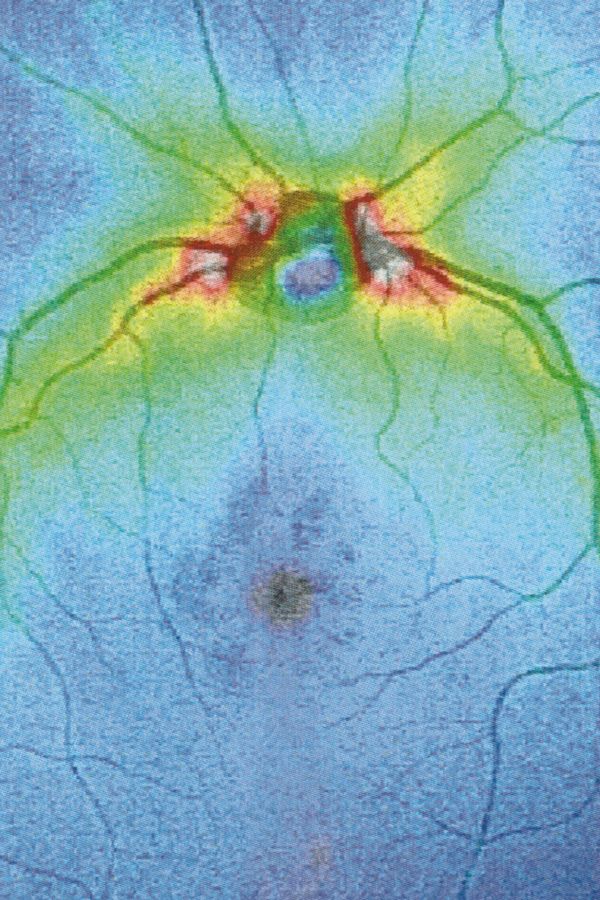

When we learn to speak, we are immersed in systems of discourse that pre-exist us and will survive us. So it is with seeing. Between us who observe and the world, there is inserted the set of discourses that constitute visuality and that make it different from vision. Between the retina and the world, a screen of signs is inserted, a screen composed of all the multiple discourses on vision constructed in the arena of collectivity. This screen casts a shadow, Jacques Lacan calls it “scotoma”, “a stain”. Because when we look through the screen, what we see is trapped in a net and can only project towards us the shadow itself of its signifier, its meaning. In the visual field, something cuts, cuts through, parallel to the pupil. It is the fabric of practices, habits, languages, all linked to the reality of representations, with which the meaning of what we see is casted as a shadow.

Collirio is an exercise in comparison. On the one hand, there is the cut left from my lisergic experience, on the other the one described by Lacan, analogue and yet still of opposite function.